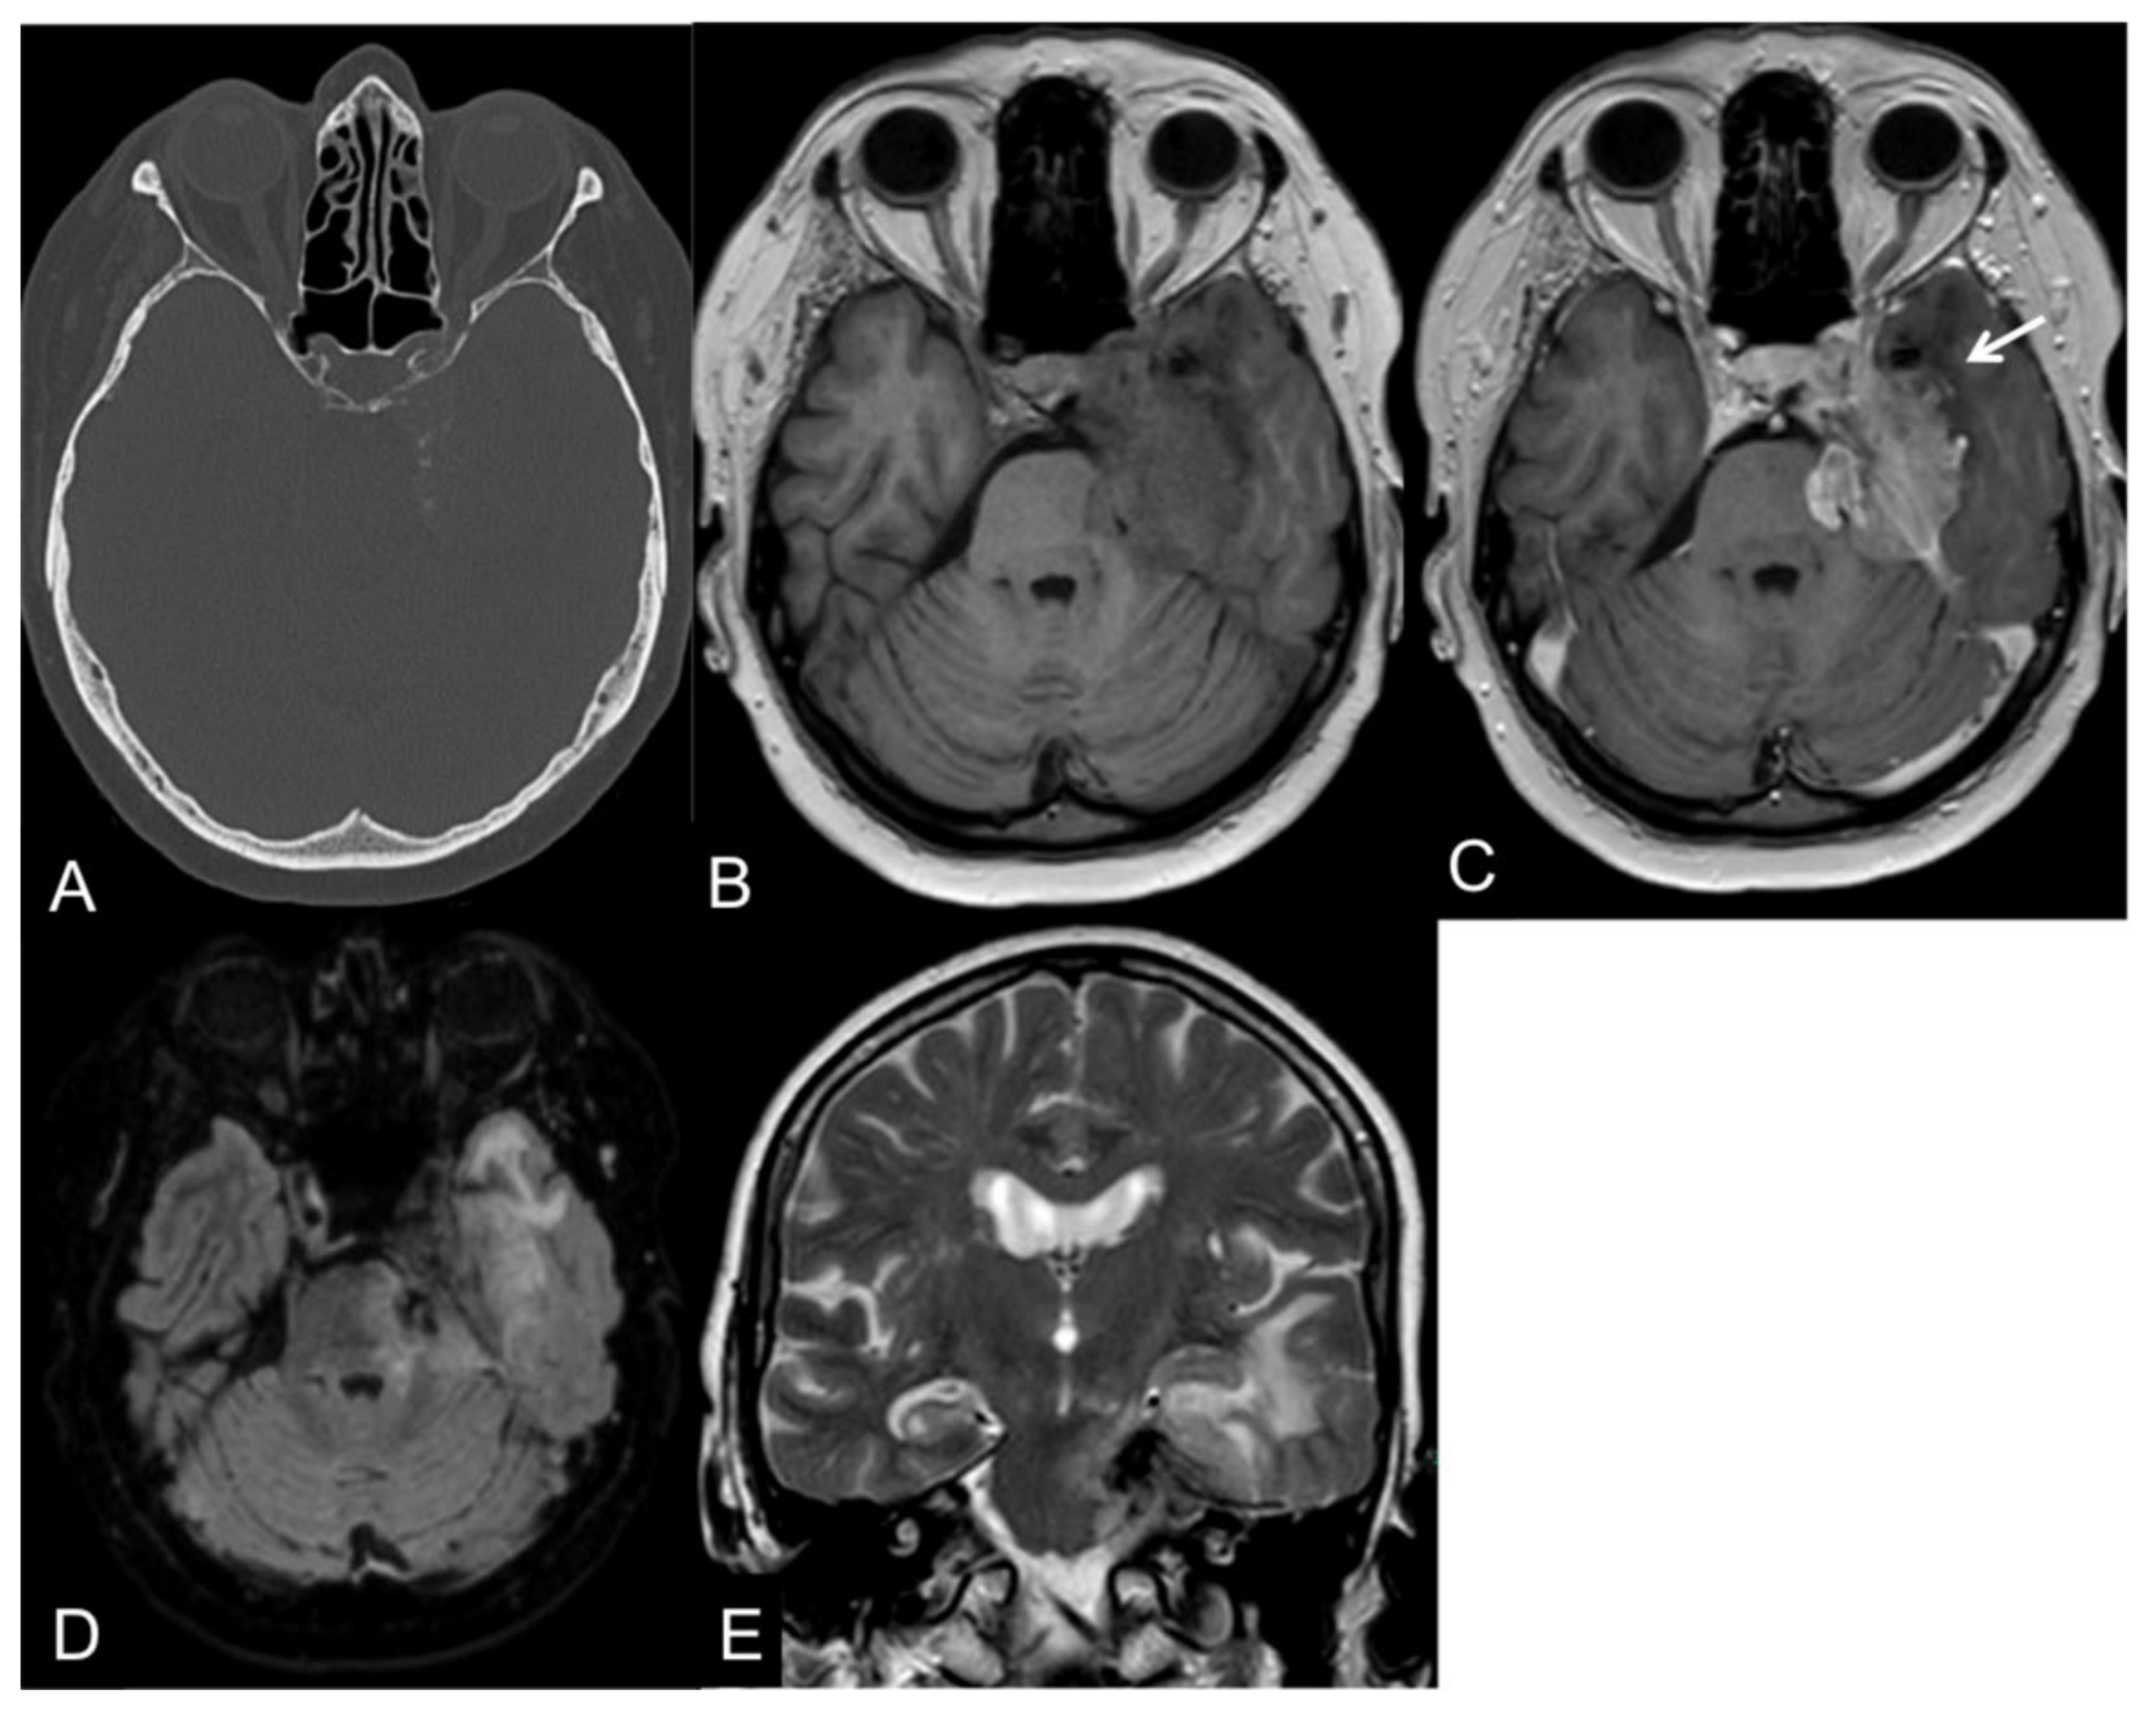

5. Radiological Features